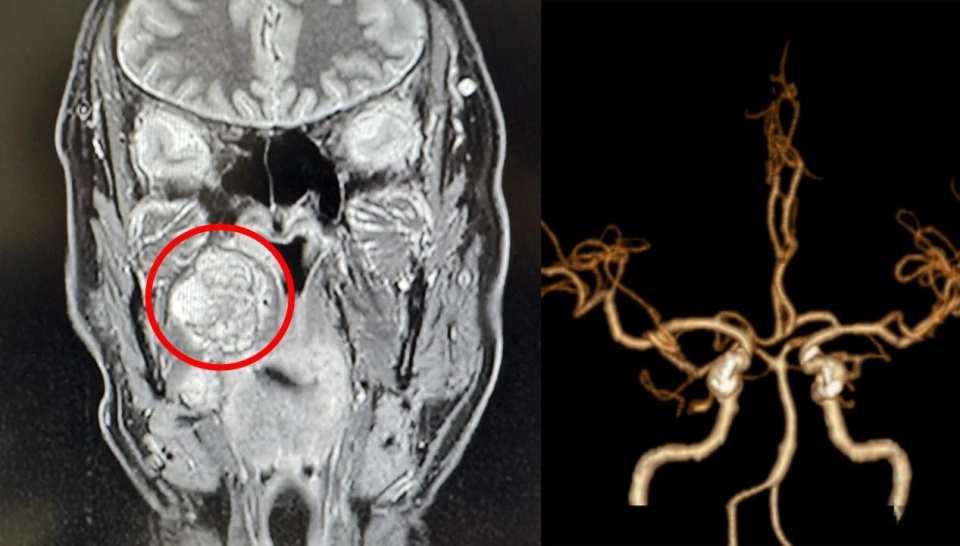

经颅底磁共振(MRI)检查,患者的右侧颅底及咽旁间隙,赫然藏匿着一个直径约4厘米的肿瘤。面对如此复杂高危的病例,泰康同济耳鼻咽喉科团队经过周密评估,认为手术切除是解除患者病痛、防止病情恶化的根本方法。

“这个肿瘤所处的位置堪称人体解剖的‘危险三角区’。”耳鼻咽喉科王美荣主任介绍,肿瘤深藏在颅底与咽旁间隙,位置极其隐蔽,周围密布着颈内动脉、颈内静脉、舌神经、舌下神经、副神经以及多个重要的颅神经分支。术中可能需打开下颌骨才能充分暴露切除肿瘤,这也预示着术后可能出现下颌关节紊乱、长时间无法咀嚼甚至终身无法正常咀嚼过硬食物的后遗症,任何手术操作都如同在刀尖上跳舞。